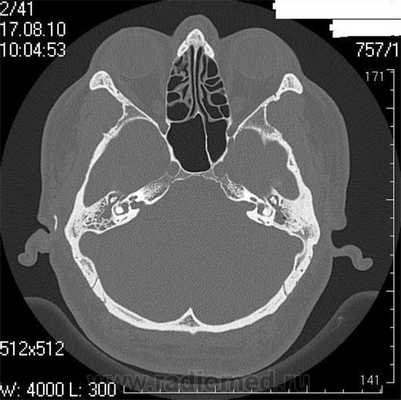

КТ-признаки злокачественной опухоли височной кости предопределяются происходящими в ней патоморфологическими изменениями. Так, наличие опухолевых масс в среднем ухе на КТ проявляется нарушением пневматизации полостей среднего уха (рис. 1). Рисунок 1. Лангергансоклеточный гистиоцитоз. Аксиальная проекция правой височной кости. Отсутствует пневматизация полостей среднего уха за счет наличия опухоли (1), вызывающей обширные деструктивные изменения в пирамиде. Цепь слуховых косточек сохранена (2). Степень выраженности данного КТ-симптома обусловлена размерами самой опухоли и ее точной локализацией в височной кости. Нарушение пневматизации полостей среднего уха не является специфичным для новообразований и постоянно встречается при других заболеваниях среднего уха, в первую очередь при остром и хроническом средних отитах.